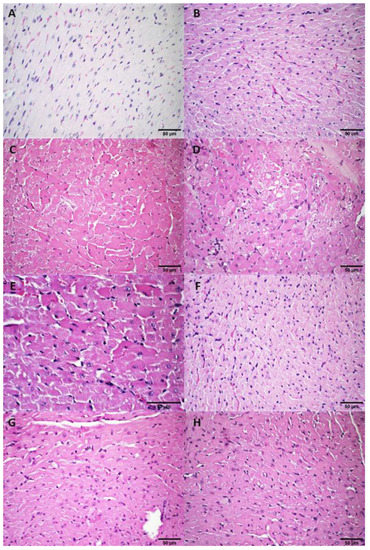

3.2.4. Histological Analysis

3.3.2. Histological Analysis